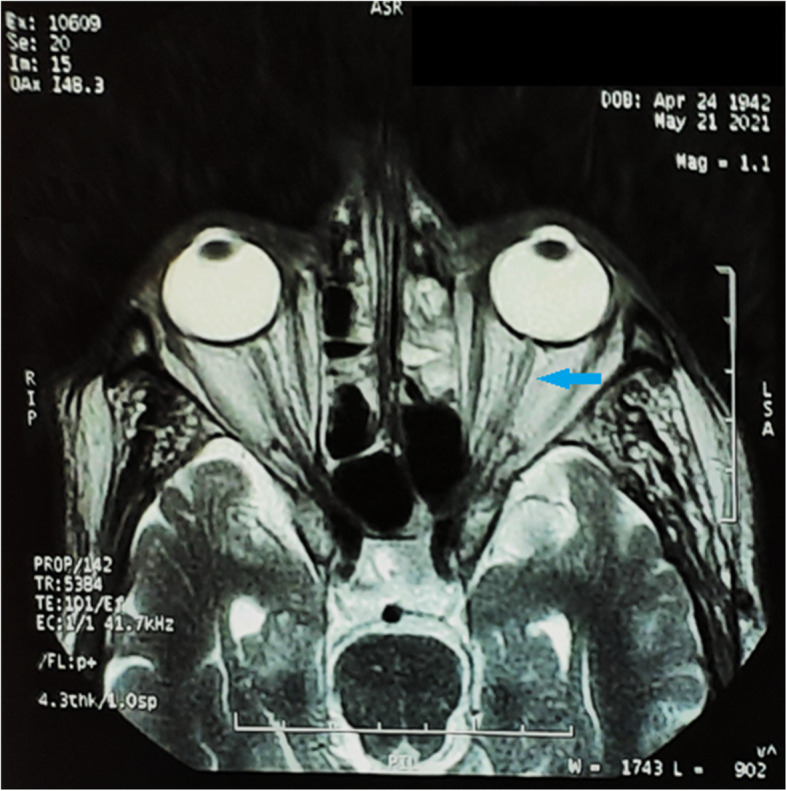

Fig. 2.

Axial MRI without contrast along the maxillary sinus showing bilateral sinusitis yet more on the left side with hypo intense margins that goes radiologically with fungal infection with heavy metals deposition and hyper intense center that represents bacterial nature

Fig. 3.

Blue arrow along non contrast MRI T2 WIs highlighting mild form of left optic neuritis

MRI paranasal sinuses performed prior admission at 3 Tesla high field MRI unit revealed near pan sinusitis especially along bilateral frontal, ethmoidal, maxillary sinuses, and left sphenoid. Both ethmoid sinuses show predominantly fungal sinusitis with bacterial sinusitis, while the left maxillary show more bacterial but with fungal component. No abnormal extension of the inflammatory process towards the cavernous sinus regions was noted. Both orbits had normal appearance except for mild form of the left optic neuritis that needed post intravenous contrast study that was inapplicable secondary to renal impairment (Figs. 2 and 3).